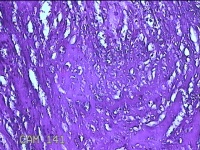

胎盘组织

性别

女

年龄

31岁

临床诊断

提前自然临产伴有足月产

一般病史

停经39+1周。

标本名称

大体所见

灰白暗红色胎盘组织19x15x2.3㎝一个,表面光滑,血管清晰,颜色发暗,绒毛面结节状,轻度糜烂,表面有少许凝血块,切面见绒毛内有部分淤血,边缘蜕膜可见多个小血肿,脐带49x1.3x0.8㎝,切断脐带,见脐血管内有凝血块。

图2